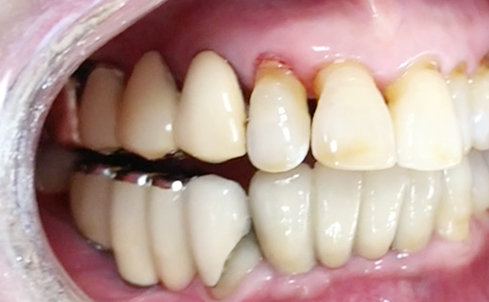

Implants/Bone Grafting

Partial edentulous clinical cases